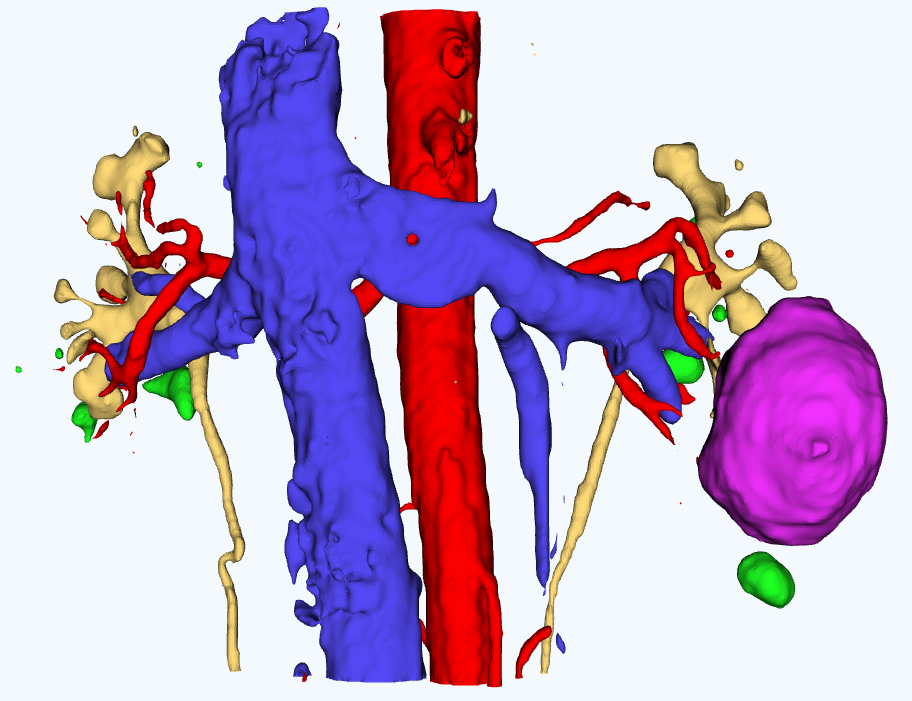

для планирования оперативного вмешательстваСервис создает интерактивные виртуальные 3D модели пациента на основе снимков компьютерной томографии

Персонализированная анатомия

Сервис позволяет выделить расположение артерий, вен, мочеточников, новообразований и паренхимы почки пациента.

Работа с 3D моделью

Врач может работать с 3D моделью для изучения анатомических особенностей пациента